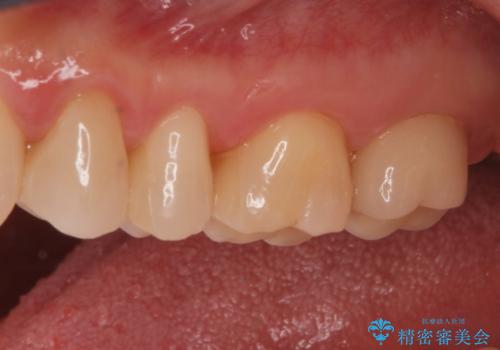

拡大鏡下でメタルを除去し虫歯がないことを確認してから白い詰め物、被せ物で治療を行いました。

- ジルコニアクラウンスタンダード・仮歯 12.1万円 e-maxインレー・7.7万円費用は治療当時の料金となります

適合の良い詰め物、被せ物が入りました。